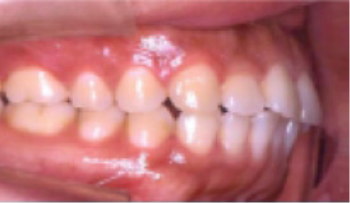

• 총생(Crowding) 치아가 삐뚤게 남.

Before

After